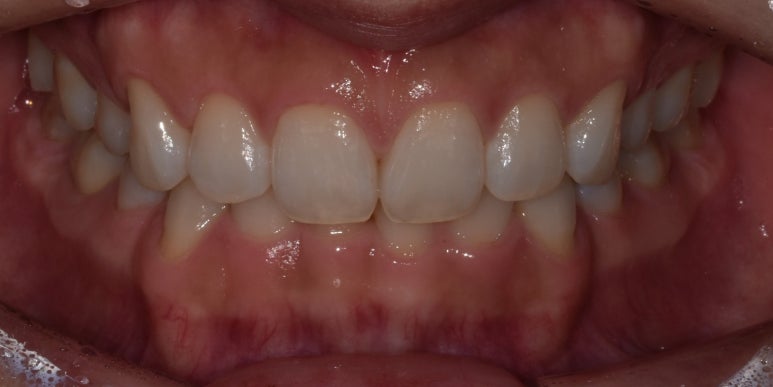

잇몸성형 시술 사례

(전) 2022-12-08 (후) 2022-12-22

특히나 저희 디데이치과의 경우 잇몸성형 1회 시술이 끝나고 2주 후에 리터치까지 진행해

개선된 잇몸라인이 더욱 더 확실하게 자리를 잡도록 도와드리고 있습니다.